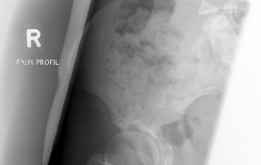

Beyond the AP pelvis, the False Profile view of Lequesne and de Sèze is mandatory to evaluate anterior coverage, which is frequently deficient in DDH. This view allows for the measurement of the Anterior Center Edge Angle (ACEA). In this patient, the ACEA is markedly reduced, correlating directly with her positive anterior apprehension test and the anterior location of her labral tear. We must also scrutinize the AP radiograph for signs of acetabular retroversion, such as the crossover sign, ischial spine sign, and posterior wall sign. Dysplasia is rarely a simple lack of lateral coverage; it is often a complex, multi-planar deformity where the acetabulum is not only shallow but also maloriented in the sagittal and axial planes.